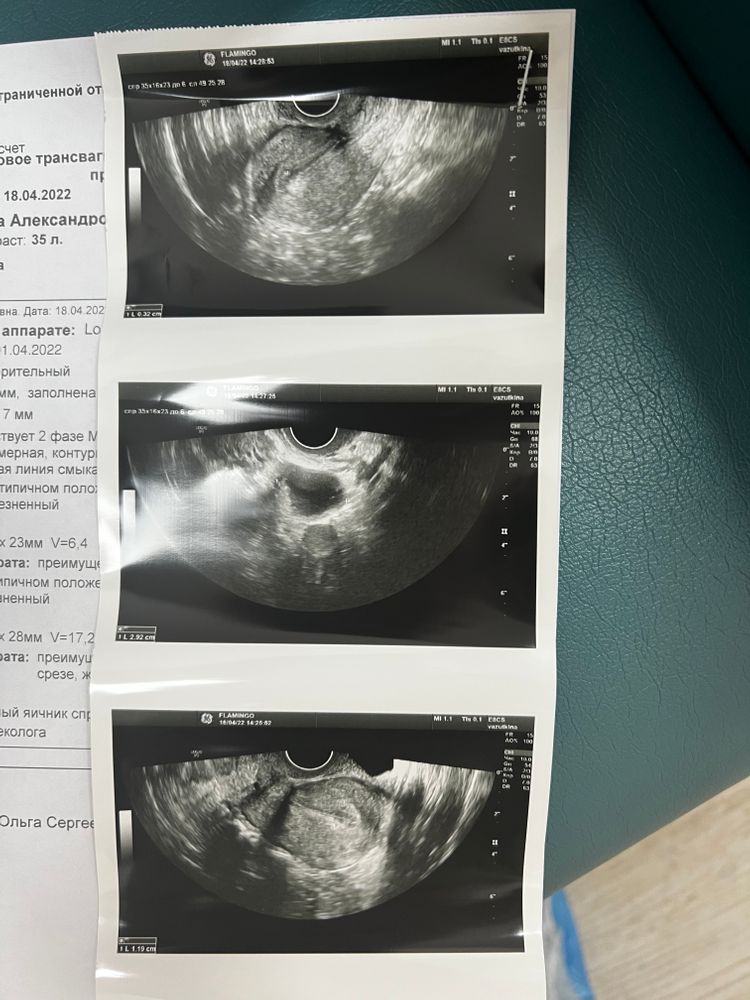

Сегодня зафиксировали по узи желтое тело 29 мм.

Кстати, фото тестика на овуляцию 15.04 и сегодняшнее узи )))